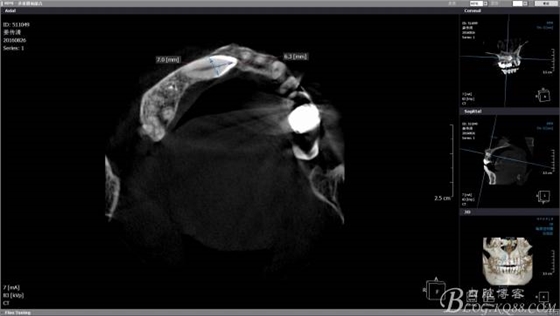

CBCT檢查尖牙牙冠靠近鼻腭神經(jīng),牙冠靠腭側(cè)且骨皮質(zhì)較薄,牙根靠唇側(cè),雖然走唇側(cè)拔除阻生牙有一個很好的視野,但是考慮到微創(chuàng)的理念和加上之后會開展種植手術(shù),所以堅決不走唇側(cè)去破壞骨皮質(zhì)。

CBCT上模擬T形分壓,測量長度,分離牙冠的時候長柄裂鉆就是我們手中的尺子,分冠時候一定切忌老老實實按照圖中的7mm去分冠,很容易穿透唇側(cè)骨板,一定要向做上頜竇提升一樣差個1mm為最合適。